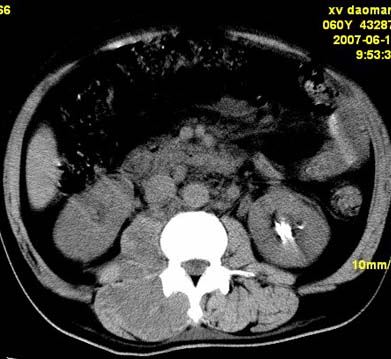

以下是引用还珠格格在2007-6-26 15:05:00的发言:[br]右侧腰大肌、同侧竖脊肌明显肿胀,呈不均匀密度减低影,右肾受压右上前移,脂肪间隙部分消失,另左侧肾盂内可见高密度影,是结石还是造影剂? 不知道病人用造影剂没有?考虑 右侧腰大肌及右侧竖脊肌寒性脓肿形成。[br][br][本贴已被 还珠格格 于 2007-6-26 15:21:35 修改过]

以下是引用小初学者在2007-6-26 15:42:00的发言:[br]1\\右侧腰大肌、同侧竖脊肌脓肿[br]2\\左侧肾盂结石

以下是引用刘明在2007-6-26 16:00:00的发言:[br][br]右侧竖直肌及腰大肌肿胀,脂肪间隙难辨,腹膜后血管旁见多个肿大淋巴结影,椎体附件右侧有压迫吸收、未见硬化迹象,考虑椎旁冷脓肿可能[br]左侧肾盂内可见高密度影,周围有毛刺,本图象是平扫,不是增强,应该是结石[br]